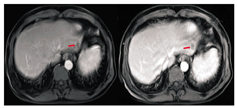

内科治疗:患者于2015年4—6月接受3周期mFOLFOX6方案(乐沙定+氟尿嘧啶+亚叶酸钙)化疗。全腹部MRI(2015年6月)提示:乙状结肠病灶段肠壁变薄,周围脂肪间隙累及加重。肝转移灶较前略缩小,盆腔多发异常信号影,不能排除转移,见图2。肿瘤标志物:CEA为68.39 μg/L,血清CA19-9 < 0.60 U/ml,CA72-4为1.09 U/ml。疗效评估:病情稳定(SD)。

MDT运行病例讨论:患者完成3周期化疗后,综合评价疗效为:SD。未出现肠道急症症状,肿瘤标志物无明显降低。患者手术意愿强烈,目前一般状况良好,能够耐受手术。建议患者行骨扫描,明确盆腔是否为转移灶。经评估,原发灶及转移灶有R0切除的可能,若无盆腔转移,可考虑同期或分期切除原发灶及转移灶。